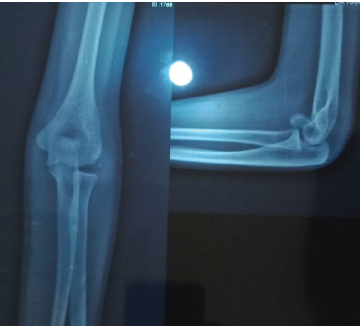

Neglected Anterior Elbow Dislocation without Fracture: An Unusual Case in an Adolescent

Gueye Alioune Badara , Mouhamadou Moustapha Niane , Kalifa Ababacar Faye , Yacine Sock , Charles Valerie Alain Kikpe

………………………………p.182-184